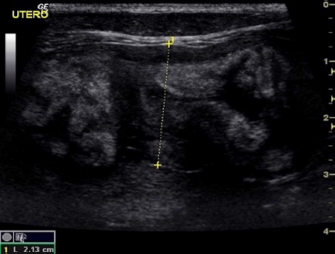

Eight intact female cats were referred for the treatment of FAC between 2015 and 2020. Ages at admission ranged from 8 to 12 months (Table 1). Four cats were domestic shorthair (C1, C2, C5, and C8), two cats were Maine Coon (C3 and C6), and two were Persian (C4 and C7). None of the cats received exogenous progestins but had a history of recent heats. Four cats (C5, C6, C7, and C8) had been mated and were between the 25th and 32nd day of pregnancy at presentation. The mammary glands were bilaterally enlarged, and no milk secretion was detected. Skin ulceration, inflamed, and painful mammary glands were present in six cases (C1, C2, C3, C5, C7, and C8) (Fig. 1a and b). General signs (tachycardia, lethargy, and anorexia) were strongly related to these changes. The diagnosis of FAC was based on clinical symptoms. Fine-needle aspiration biopsy of the mammary tissue was performed to support the clinical diagnosis. The combination of glandular-epithelial tissue and mesenchymal cells and the absence of prevalent immune cell populations in the cytologic smears allowed to exclude malignant growth or mastitis. Ultrasound examination of the mammary gland and doppler was employed to evaluate the structure and vascularization of the enlarged gland. FAC presented mainly as a well-circumscribed solid mass of granular, slightly hyperechoic texture, with regularly delimited margins. There was a uniform distribution of vascularity. Anechoic areas were present in the parenchyma and outside the margins (Fig. 2). Owners gave their consent to conservative treatment to preserve fertility and the integrity of the mammary glands. Mastectomy was not performed in any cases. Non-pregnant cats (C1, C2, C3, and C4) were treated on two consecutive days with subcutaneous injections of 15 mg/kg Aglepristone (ALIZIN; Virbac, Carros, France). The treatment was continued weekly with a single injection until the resolution of signs. If signs of ulcers, inflammation, or necrosis were evident in at least one mammary gland, 12.5 mg/kg q 12 hours of amoxicillin / clavulanic acid tablet formulation (SYNULOX; Zoetis, Rome, Italy) and 0.1 mg/kg q 24 hours of meloxicam (MELOXORAL oral suspension 0,5/ml; Dechra Veterinary Products, Turin, Italy) for the first day, followed to 0.05 mg/kg q 24 hours was given for 5–6 days. Furthermore, an oral dietary supplement containing maltodextrin and bromelain (BROSPET; Aurora biofarma, Milan, Italy) was administered once a day for the treatment period. Ulcers were treated topically twice daily with a cream containing hypericum and neem extract (HYPERMIX; Rimos, Mirandola, MO, Italy). The enlarged mammary glands were daily massaged with an emollient gel based on Aloe vera (ALOPET GEL; linea Angel Ariel, Grancona, VI, Italy). Two of the four pregnant female cats were treated with the same schedule for the severe enlargement and ulceration of the mammary glands (C5) and early signs of fetal resorption, deduced by the slow heart rate and the increased echodensity of amniotic fluid (C6). After 1 week, they presented bloody vaginal discharge, and ultrasound revealed four placental remnants in a cat (C6) (Fig. 3). Cloprostenol (ESTRUMATE; MSD Animal Health, Segrate, MI, Italy) at the dosage of 1.5 mcg/kg was given for three consecutive days to facilitate uterine emptying. Two pregnant female cats (C7 and C8) were treated with the schedule less the aglepristone drug to preserve the litters. In all the cases studied, after 2–3 weeks, the mammary gland reduced in size, and no ulcers or necrotic areas were detected, and after 4–5 weeks, the lesion was not more recognizable. At term, pregnant queens C7 and C8 delivered four and three kittens, which were normally nursed and weaned after 40 days (Fig. 1c). The case series is summarized in Table 1. A 1-year follow-up reveals no recrudescences of FAC in treated animals.

Fig. 3. Case C6. A pregnant 1-years-old Maine Coon cat with FAC presenting placental remnants at ultrasound after the treatment with aglepristone.